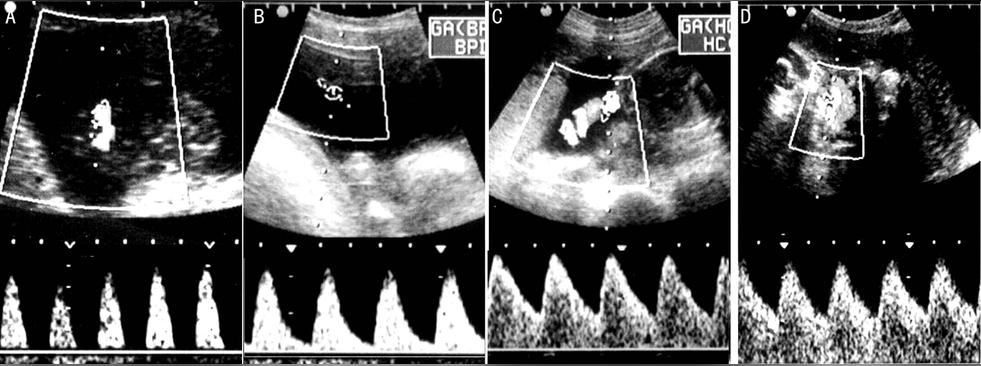

動(dòng)脈血流收縮期峰值(A或S)和舒張末期的谷值(B或D),計(jì)算出S/D或A/B比值,同時(shí)還可計(jì)算阻力指數(shù)(RI=A-B/A)和搏動(dòng)指數(shù)(PI=A-B/均值A(chǔ)、B)。正常妊娠時(shí),上述這些數(shù)值隨孕周而下降,通常24周以前A/B>4,30周后A/B小于3.0,RI小于0.68

臍動(dòng)脈血流收縮期最大血流速度(S)與舒張期末期血流速度(D)的比(S/D、A/B),觀察 S/D(A/B)比值的動(dòng)態(tài)變化,可判斷胎盤的發(fā)育情況。在正常情況下隨胎兒發(fā)育,胎盤逐漸增大.血管阻力逐漸減小,S/D(A/B)比值逐漸減小。從孕25周到41周S/D比值幾乎呈直線從 2.8降至 2.2。胎兒宮內(nèi)發(fā)育遲緩、胎盤和胎兒發(fā)育不良,胎盤不增大,血管阻力不下降。故S/D比值不下降。在臨床上S/D不按規(guī)律下降,或反而升高,說(shuō)明胎兒發(fā)育不良。

使用臍動(dòng)脈血流檢測(cè)儀,在胎兒肢體側(cè)探測(cè)臍動(dòng)脈血流,內(nèi)置軟件根據(jù)所測(cè)S/D,PI、RI、FUR血流指標(biāo)將自動(dòng)測(cè)出血流阻抗分級(jí)

正常妊娠時(shí)胎兒的S/D、RI值隨著妊娠時(shí)間推移呈降低趨勢(shì),尤其S/D值的變化是掌握胎兒發(fā)育是否正常的重要指標(biāo)。